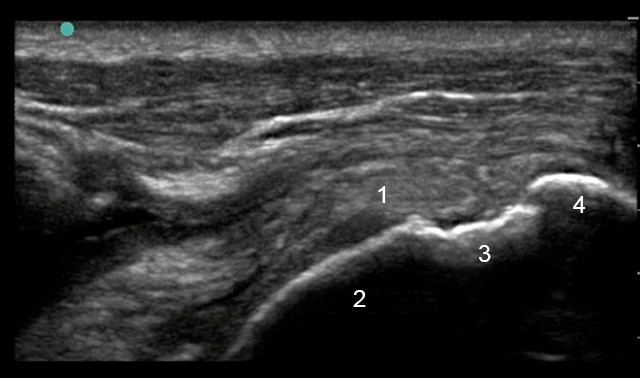

Shoulder Rotator Cuff Post-Operative Longitudinal Image

1. Supraspinatus

2. Humeral Head

3. Foot Print

4. Greater Tuberosity (GT)